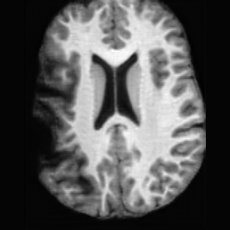

Anomaly Consistency Guidance. Fig. 6 demonstrates the effectiveness of the proposed Anatomy Consistency Guidance (ACG) on bidirectional editing. Without ACG, the generated brains exhibit noticeable and unrealistic anatomical deformations in non-lesion regions (arrow-indicated), leading to structural inconsistencies between the edited and original brains, as shown in the corresponding difference maps. After incorporating ACG, the model effectively constrains editable modifications within pathological regions, while preserving the remaining anatomy. Tab. 4 further reports their quantitative performances: removing ACG leads to a substantial degradation in all L1, PSNR, and SSIM scores, reaffirming the critical role of ACG in achieving more accurate and structurally consistent reconstructions.

Lesion Consistency Guidance. Fig. 7 illustrates the impact of Lesion Consistency Guidance (LCG) for healthy-to-pathology editing. Without LCG, the generated lesion regions appear blurry around lesion boundaries, and the pathological patterns are less distinct, resulting in ambiguous lesion localization and weak pathological expression. Incorporating LCG produces lesions with more precise localization and well-defined shapes that better align with the given lesion masks, as well as textures and contrasts that exhibit stronger pathological characteristics. These results demonstrate that LCG effectively enforces lesion-aware conditioning, enhancing both spatial and semantic consistency of the generated pathological regions.